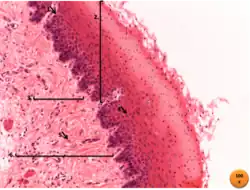

Tecido conjuntivo (azul) é visto sustentando o epitélio (roxo) do epidídimo.

Tecido conjuntivo ou tecido conectivo se refere ao grupo de tecidos orgânicos responsáveis por unir, ligar, nutrir, proteger e sustentar os outros tecidos. São responsáveis pelo estabelecimento e pela manutenção da forma do corpo.[1] Caracteriza-se por apresentar variados tipos celulares, que são separados por uma grande quantidade de matriz extracelular. Essa matriz, é responsável por conectar as células e os órgãos, dando suporte ao corpo. Além disso, é o principal componente desse tipo de tecido e consistem em diferentes combinações de proteínas fibrosas e em um conjunto de macromoléculas hidrofílicas e adesivas, que constituem a substância fundamental.[1][2]